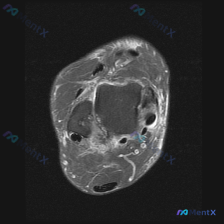

看到一份踝关节MRI的读片资料,整理了完整的分析和鉴别思路分享给大家。 病例核心影像信息 这是踝关节上方水平的轴位T2序列MRI: 1. 解剖层面:显示踝穴上方的胫骨远端干骺端、腓骨远端,可清晰识别跟腱、胫骨后肌腱、趾长屈肌腱、踇长屈肌腱、腓骨长短肌腱等结构 2. 核心阳性发现:内踝后方胫骨后肌腱的...